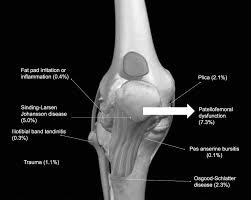

A growth plate is a layer of cartilage near the end of a bone where most of the bones growth happens. Sinding-Larsen Johansson Disease SLJ is a possible cause of knee pain in 8-to-13-year-old active individuals. Figure 1 Anatomy of Sinding-Larsen-Johansson disease.

Sinding-Larsen-Johansson SLJ syndrome is pain at the bottom of the kneecap patella. This is the Sinding-Larsen-Johansson disease SLJD and has been used as an umbrella term for the syndrome that causes pain of the inferior pole of the patella accompanied by fragmentation of the pole or a calcification at the pole. What is Sinding-Larsen-Johansson disease.

This can occur in growth spurts or overuse from running jumping or. Sinding-Larsen-Johansson disease is a relatively uncommon condition of the knee affecting adolescents. Sinding-Larsen-Johansson syndrome is an osteochondrosis of the inferior pole of the patella and is often bilateral.

Sinding-Larsen-Johansson disease also known as Sinding-Larsen disease or Larsen-Johansson syndrome affects the proximal end of the patellar tendon as it inserts into the inferior pole of the patella. This can occur during growth spurts or overuse from running jumping or squatting. How is it treated.